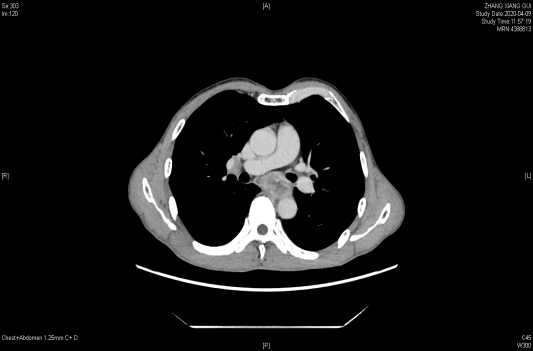

一个人生病时,回想这一生,什么对他来说最重要呢? 2020年,是马先生抗争病魔的第5个年头。 “我老公是15年12月份...